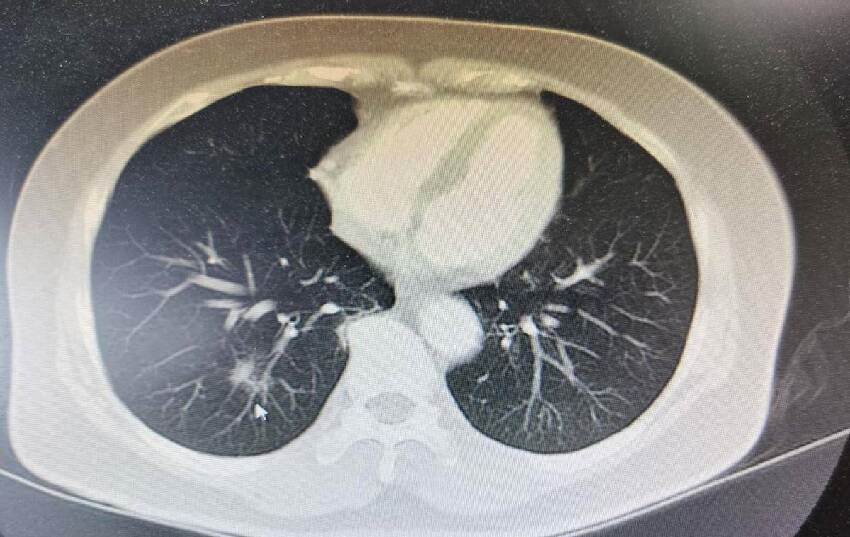

部分人對痛感沒有那麼明顯,覺得雙腳疼痛,可能是走路走多了,不太會引起重視。建議大家這個時候可以選擇去醫院拍一下CT照片,檢查一下肺部是否有問題,早發現早治療,以免延誤病情。